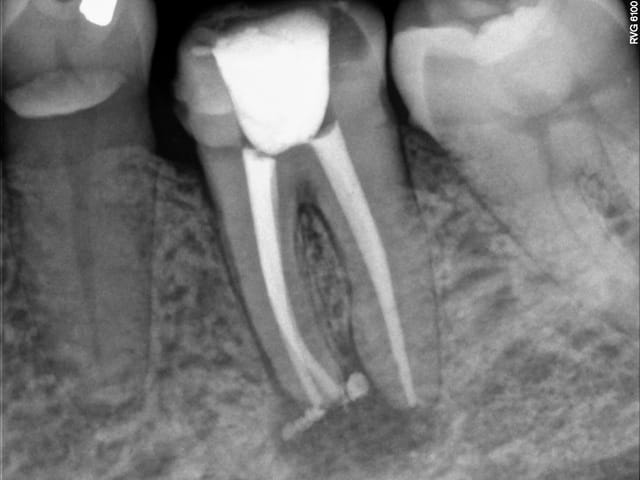

Voilà ce patient a consulté en Juillet pour une douleur à la mastication. Je regarde la radio, belle pêche sous les racines, en bouche, une fêlure traversant la dent dans le sens MD. A votre avis que faire dans ces cas et comment évaluez vous la réussite ou non de l'endo - CCC dans ces cas? Il n'avait aucune douleur quand j'appuyais transversalement de sur la moitié linguale ni sur la moitié vestibulaire (vers l'extérieur de la dent, pour "séparer" les dent).

Bref je fais l'endo, et lisant de plus en plus de choses sur le sans-tenon (surtout le risque de fracture supérieur qu'il engendrait par perte de substance dentinaire) je me suis lancé dans un "Nayyar" core, compo descendant dans les entrées canalaires et par dessus une CCC.

Ci-joint les radios.

PS: Légère extrusion de pâte en distal, j'ai un peu forcé sur le Mac Spadden, faut que je m'équipe du système B...